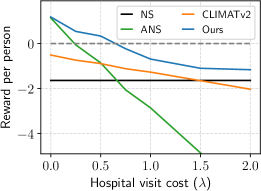

As the cost-related parameters, and , are key factors in our reward function, we aimed to quantitatively assess their impacts on our method. Specifically, we conducted two experiments involving our proposed methods, CLIMATv2, ANS, and NS policies. In the first experiment, we varied the hospital visit cost, , while keeping the MLAC, , unchanged. In the second experiment, we reversed the settings.

We present the results of the first experiment in Figure 4a, demonstrating the association between and the RPP over year, with a fixed of . Generally, all methods exhibited a decreasing trend in the reward as the hospital visit cost increased. Compared to the mentioned baselines, our RL-based method, corresponding to the blue curve in Figure 4a, consistently gained better rewards per person with every value of . The NS policy, displayed in black, resulted in a constant reward of per person since no follow-up data was acquired. Increasing from to caused a significant drop of approximately in the RPP of the ANS policy. Our proposed method met the ANS policy at and approached the NS policy when increased.

We demonstrate the results of the second experiment in Figure 4b. The performance of CLIMATv2 and the NS policy exhibited a decreasing trend as the JSW cost, , increased while keeping unchanged . In contrast, we observed that the ANS policy generally increased in proportion to . Our policy achieved a constant reward of for , and demonstrated a linear increase for . Overall, our proposed policy gained the highest reward among the methods at any value of . For values of greater than , our method stands out as the sole approach yielding positive rewards per person.

To gain deeper insights into the trade-offs related to the cost parameters and , and their impact on the outcomes, we investigated the relationship between the relative cost and the resulting RPP normalized over the hospital cost, . Specifically, we varied the hospital visit cost parameter, , across the range , while adjusting the MLAC, , within the set . The association is illustrated in Figure 4c. We observed that exhibited an inverse, non-linear relationship with the increasing of . In other words, decreasing was beneficial for the resulting RPP. Specifically, when the ratio declines to , it becomes the critical trade-off point at which our policy begins to yield positive RPPs. The raw experimental data behind Figure 4c is shown in Suppl. Table S2